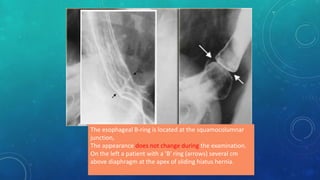

Esophageal ring due to muscular contraction. It varies

during examination and may not persist.

On the left a patient with a ring due to muscular

contraction. Notice incidental gastric diverticulum

(asterisk).

The esophageal B-ring is located at the squamocolumnar

junction,

The appearance does not change during the examination.

On the left a patient with a 'B' ring (arrows) several cm

above diaphragm at the apex of sliding hiatus hernia.